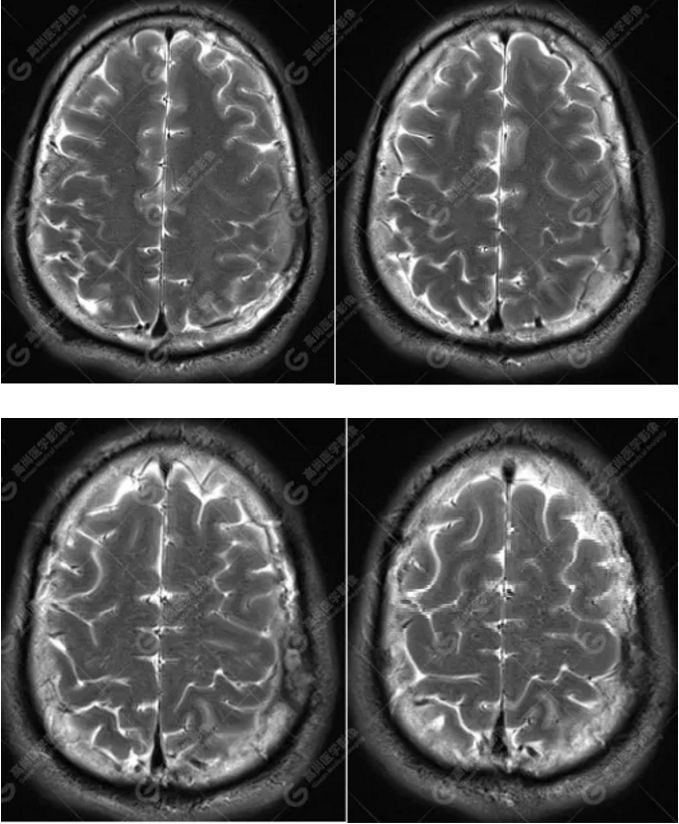

中年男性,反復(fù)出現(xiàn)手腳抽搐、暈倒伴意識(shí)喪失3年余,臨床擬診癲癇發(fā)作,后到高尚醫(yī)學(xué)影像診斷中心行MR檢查。

MR圖像

左側(cè)額頂部顱骨骨質(zhì)破壞并相鄰硬腦膜增厚強(qiáng)化,考慮Rosai Dorfman病(RDD)可能,需與朗格漢斯細(xì)胞組織細(xì)胞增生癥鑒別。

本病多累及淋巴結(jié),原發(fā)于中樞神經(jīng)系統(tǒng)而無(wú)身體其他部位淋巴結(jié)腫大者罕見,低于4%。顱內(nèi)RDD好發(fā)于中年男性,多表現(xiàn)為顱內(nèi)腦實(shí)質(zhì)外的單發(fā)或多發(fā)腫塊,好發(fā)于大腦凸面、鐮旁、鞍區(qū)及海綿竇旁,絕大多數(shù)病例都與硬腦膜密切相關(guān),腫塊多位于硬腦膜外或硬腦膜下。

總之,顱內(nèi)RDD是一種罕見的硬腦膜良性病變,若 MRI發(fā)現(xiàn)顱內(nèi)基于硬腦膜扁平或匍匐生長(zhǎng)的孤立或者多發(fā)腫塊,CT 檢查未見鈣化,而MR檢查T2WI及 DWI呈低信號(hào),增強(qiáng)明顯均勻強(qiáng)化,應(yīng)考慮到 RDD 的可能。